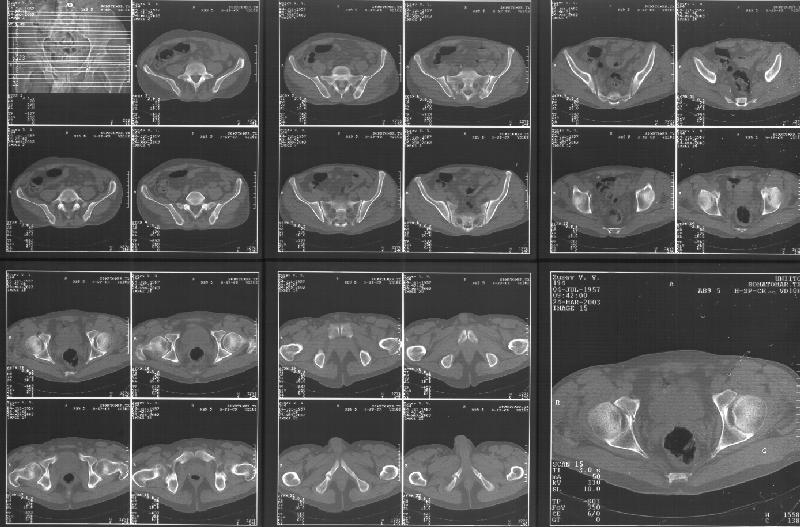

Прилагаю свежую КТ таза.

Буду признателен за комментарии и предложения по тактике.

Картинки см. ниже, левая - с экранным разрешением, вторая - полноразмерная, ~900 кб.

Полноразмрная картинка, около 900 кб